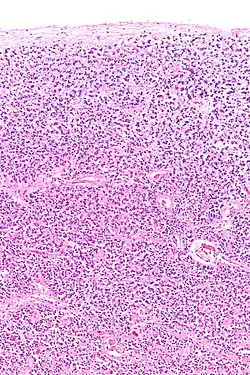

Histología

La glándula pineal está compuesta principalmente de pinealocitos que liberan melatonina, astrocitos, microglia, células endoteliales y, en algunas especies, un pequeño número de neuronas.[10]

Su estructura está formada por lobulillos separados de manera incompleta por tabiques de tejido conectivo por los que penetran los vasos sanguíneos y las terminaciones nerviosas procedentes del sistema nervioso simpático. Las células más abundantes son los pinealocitos que representan el 95% del total y están especializados en la producción de melatonina, presentan un núcleo grande, citoplasma claro y prolongaciones citoplasmáticas que contactan con los capilares sanguíneos. Otras células presentes en la glándula son las células intersticiales, son células de sostén similares a los astrocitos, con un núcleo más alargado y denso. Los llamados acérvulis cerebrales son concreciones formadas por cristales de hidroxiapatita cálcica que forman agregados extracelulares que tienden a aumentar con la edad.[11]